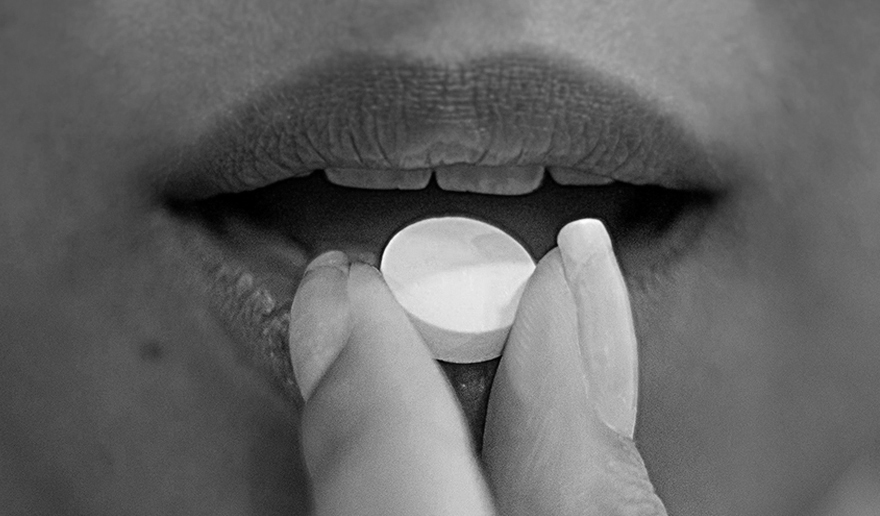

SPECIAL REPORT — Beneath the Surface: Exposing the Abortion Pill Drug Cartel